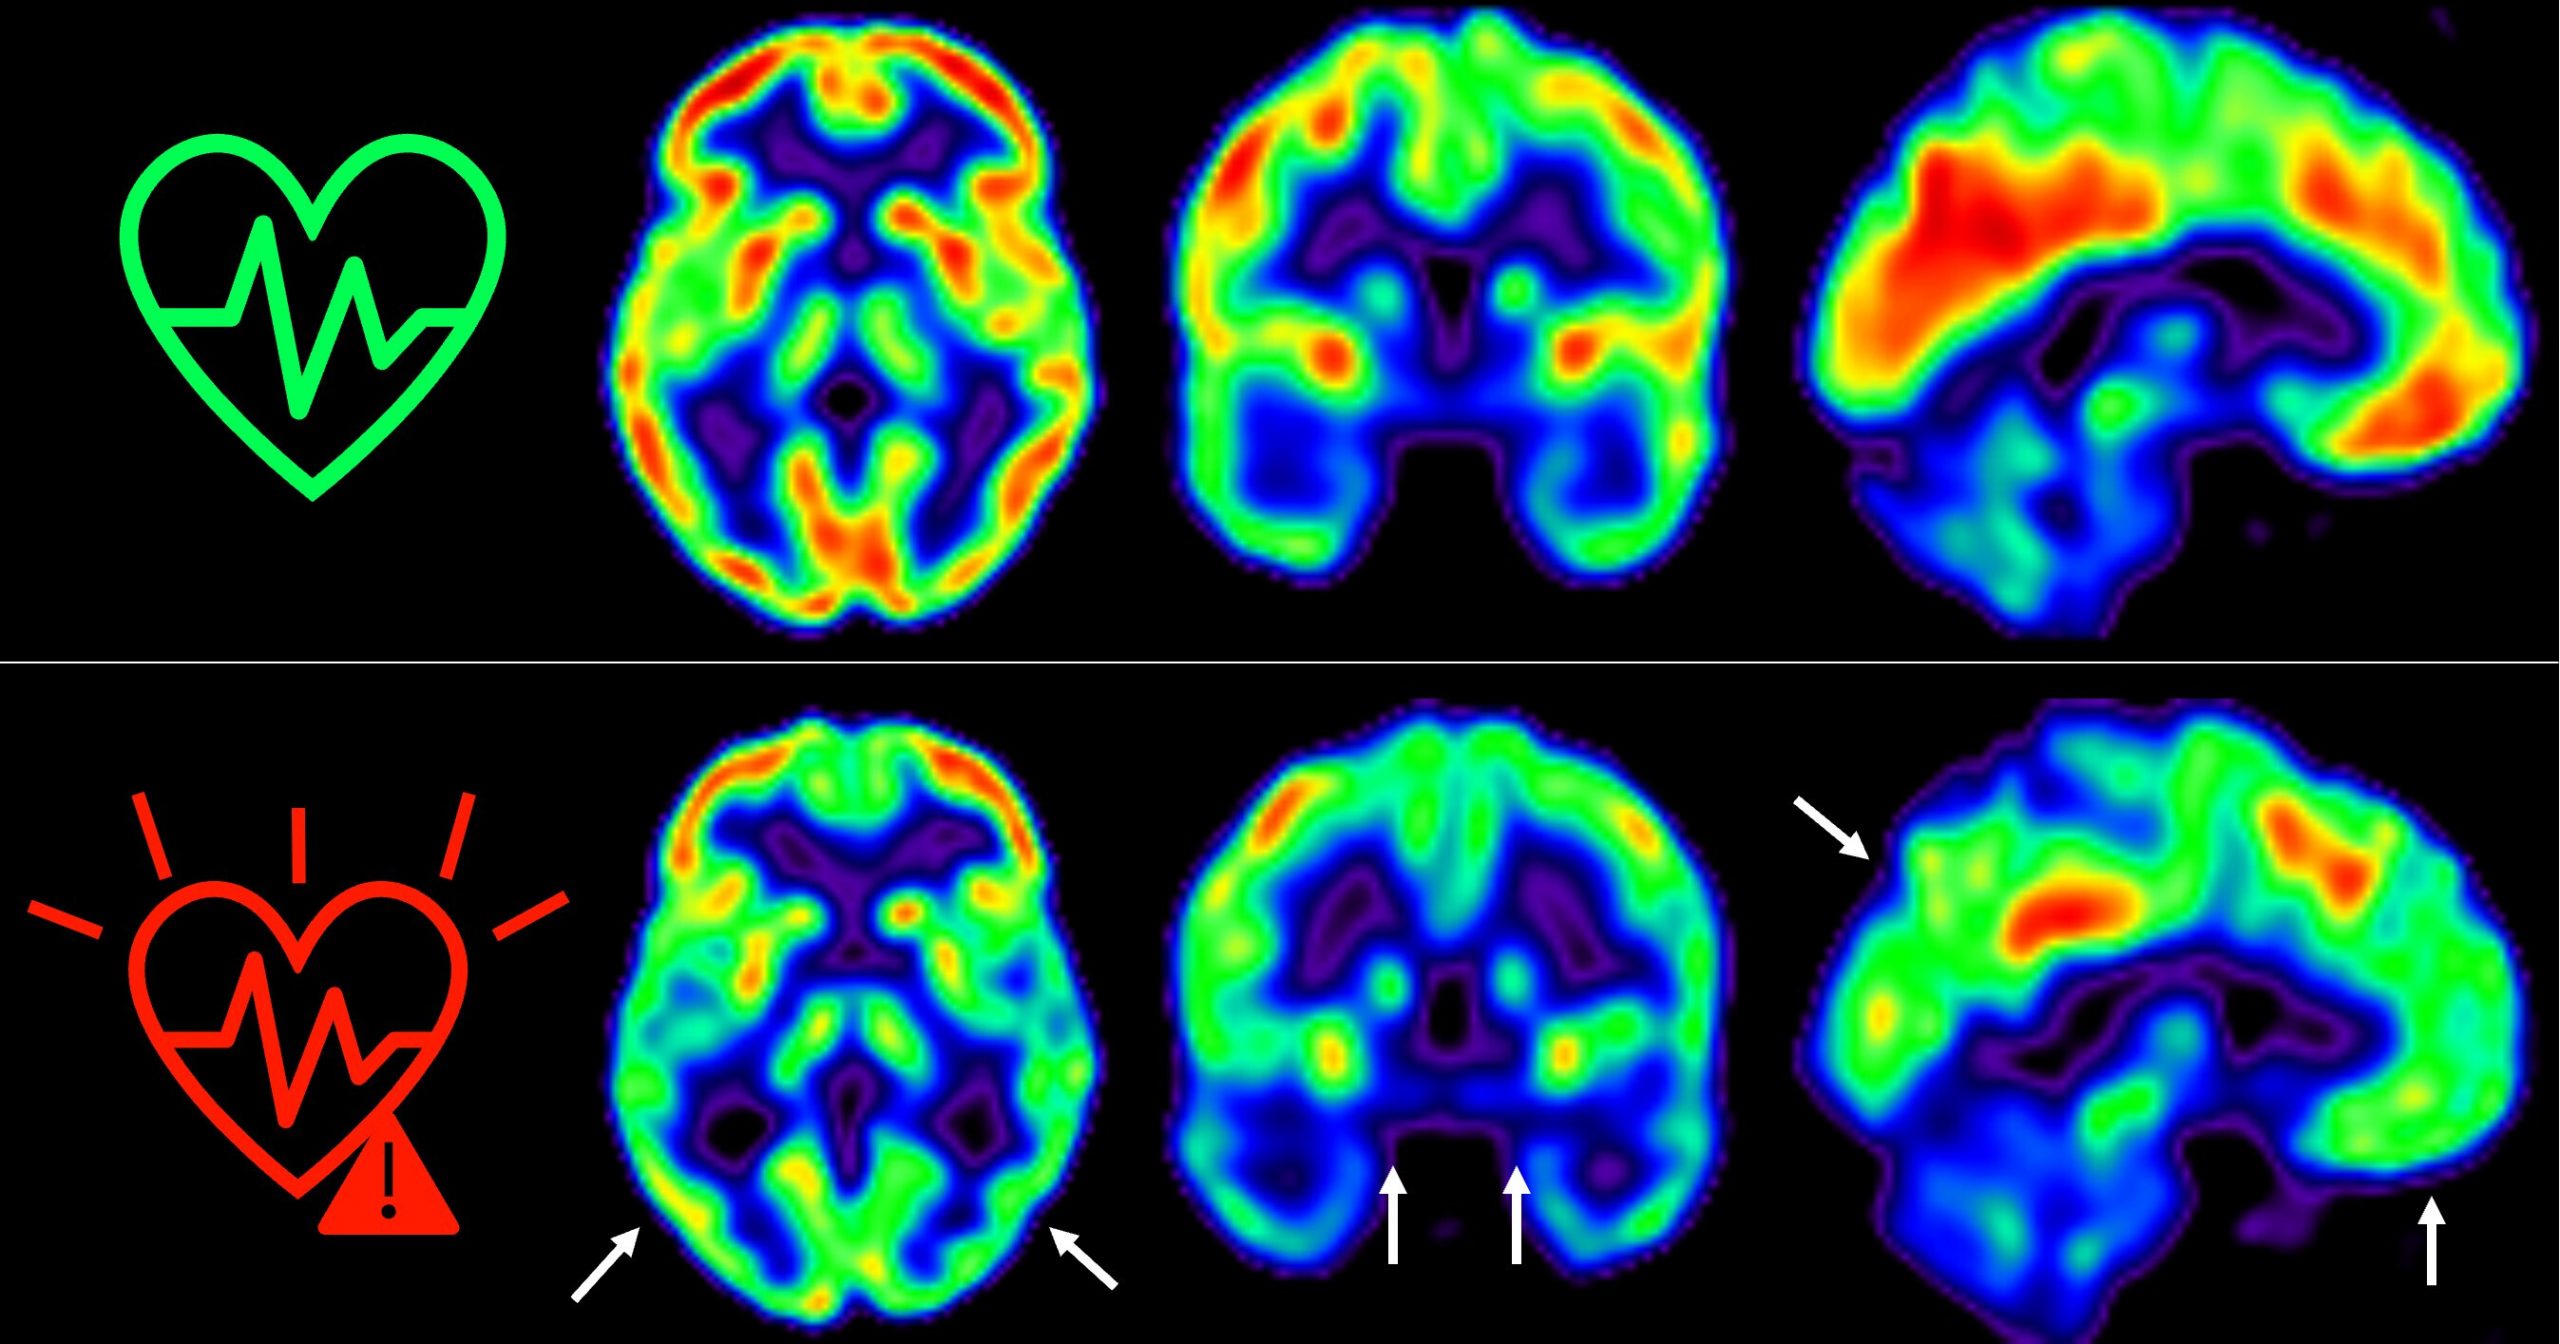

El estudio publicado en The Lancet Healthy Longevity muestra que las personas con un riesgo cardiovascular elevado experimentan una mayor disminución del metabolismo cerebral

En 2021, los investigadores del CNIC descubrieron que la presencia de factores de riesgo cardiovascular y de aterosclerosis subclínica -antes de que aparezcan los síntomas- en las arterias carótidas, que son las que suministran sangre al cerebro, estaba asociada a un menor metabolismo de glucosa cerebral.

El hallazgo sobre la glucosa fue relevante porque el metabolismo de la glucosa cerebral está considerado un indicador de salud cerebral.

Esto se ha medido a través de técnicas de imagen como tomografía por emisión de positrones (PET). Este factor es un indicador de salud.

“Hemos detectado un declive metabólico cerebral tres veces mayor que el de personas que se mantienen en bajo riesgo cardiovascular”, señala Catarina Tristão-Pereira, primera firmante del artículo y becaria INPhINIT de la Fundación la Caixa.

Además, el equipo del CNIC descubrió que la progresión de la aterosclerosis subclínica en las carótidas durante estos 5 años se relacionaba con una disminución del metabolismo en regiones cerebrales vulnerables a la enfermedad de Alzheimer. Esto se produce de manera aditiva al efecto de los propios factores de riesgo cardiovascular.